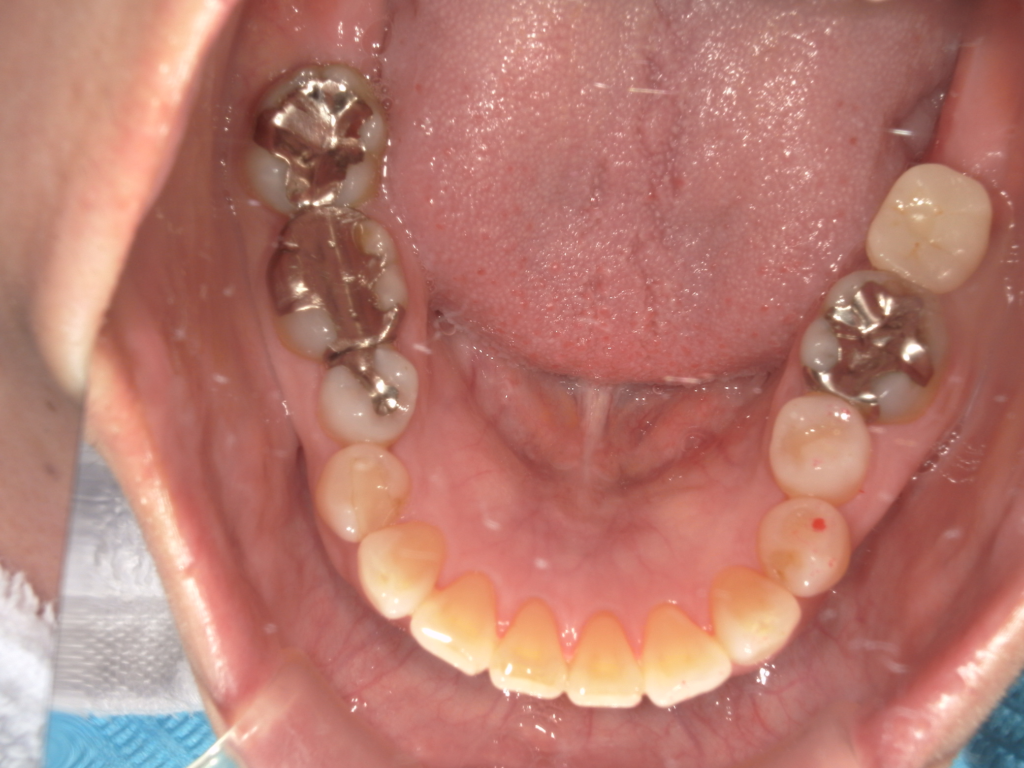

右下に2本埋め込みの手術

右下のインプラントオベになります。歯茎を切開して、ホールを、適切な位置に形成してインプラントの埋め込みを行っています。オペ中は全て滅菌操作となります。